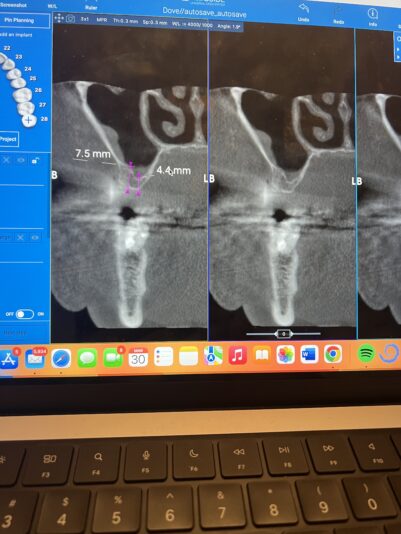

• Which approach for sinus lift would you do here

Hello everyone,

As you can see over here the anatomy of the sinus is irregular as the residual bone height is a lot higher buccally and goes down slightly palatally

In this case would you rather:

1. Do a crestal sinus left approach and place a 4.6(wide diameter)x7.5mm implant. Increasing the diameter to compensate the height in that case…